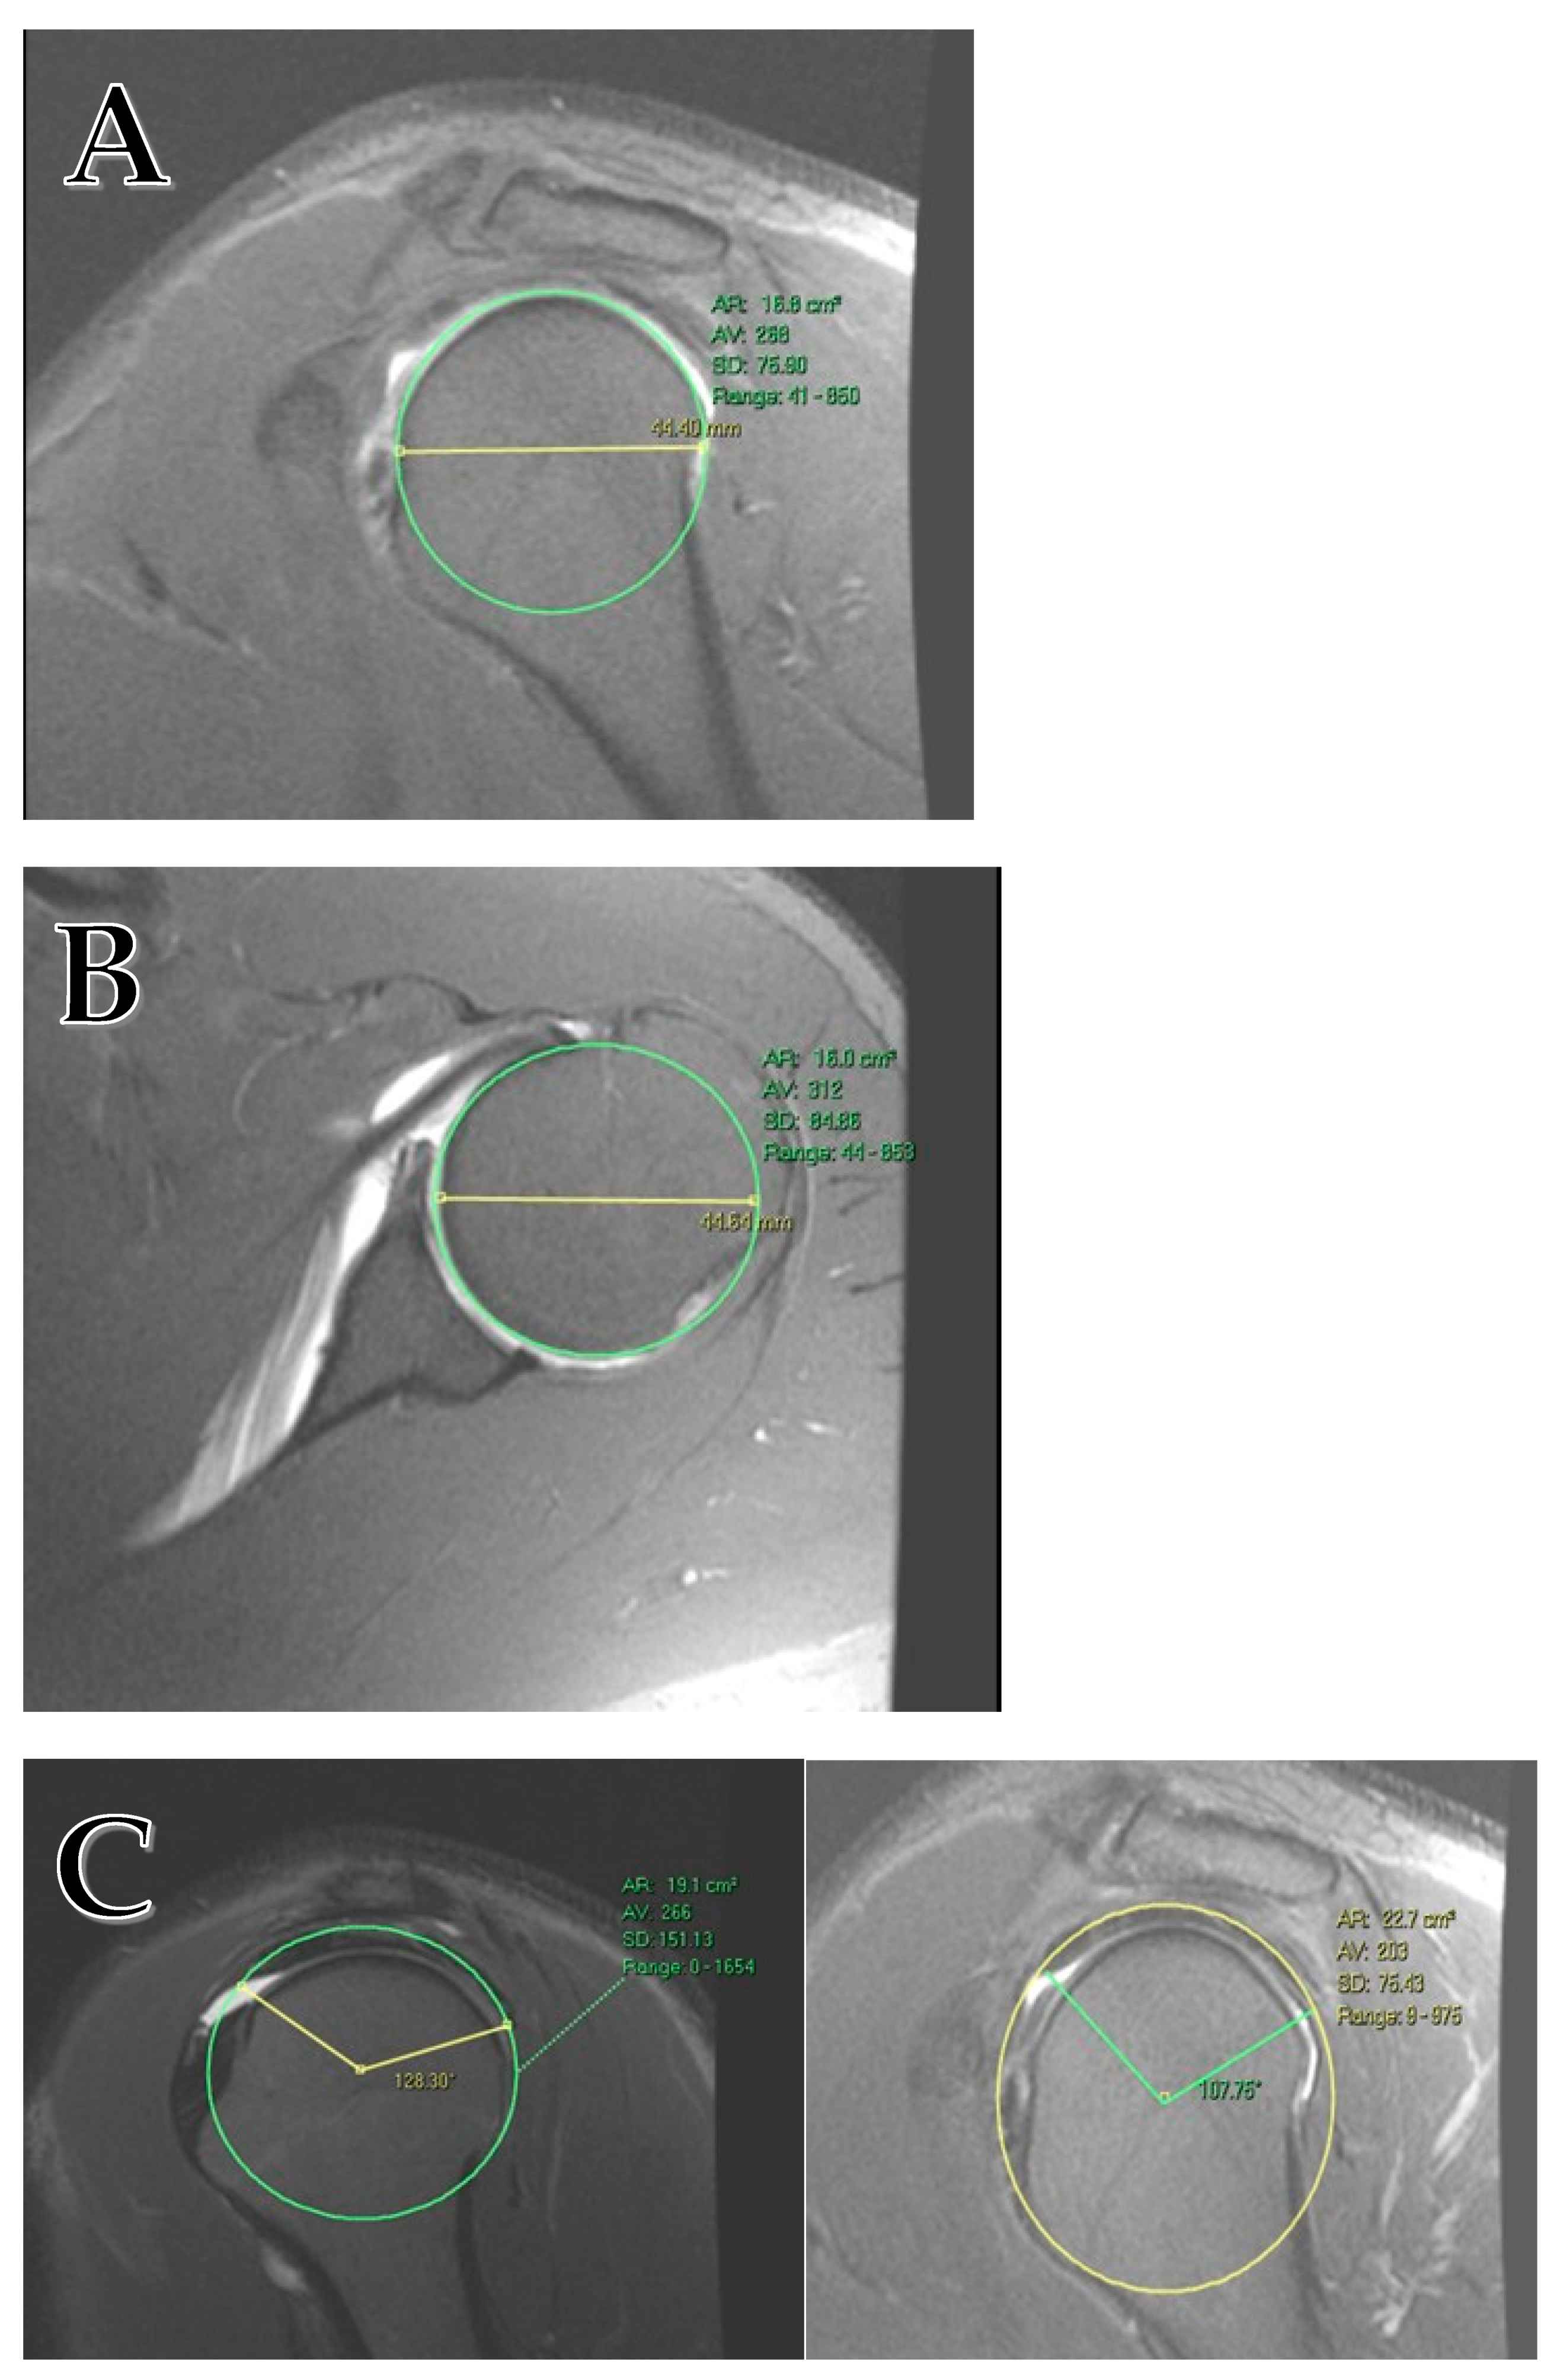

Anatomical measurements included maximal sagittal humeral head diameter (HumSG; Figure 1A), axial humeral head diameter (HumAX; Figure 1B), and the supraspinatus and infraspinatus tendon length from anterior to posterior (AP_SS_IS; Figure 1C). Rotator cuff tendon length was measured on the sagittal plane using an image depicting the greatest head diameter; the length was calculated using trigonometry. The RC measured is the confluent tendon of the supraspinatus and infraspinatus as they merge to insert into their footprint. All measurements were taken using T2 weighted MRI images (T2WI). Measures were re-evaluated and reconfirmed by a second author.

Figure 1. (A) Humeral head diameter measurement on the sagittal plane. (B) Humeral head diameter measurement on the axial plane. (C) The rotator cuff tendon is measured on the sagittal plane on the image of the largest head diameter. The RC length is calculated using trigonometry. The tendon has a hypointense signal that reflects the confluence of the supraspinatus and infraspinatus tendon.